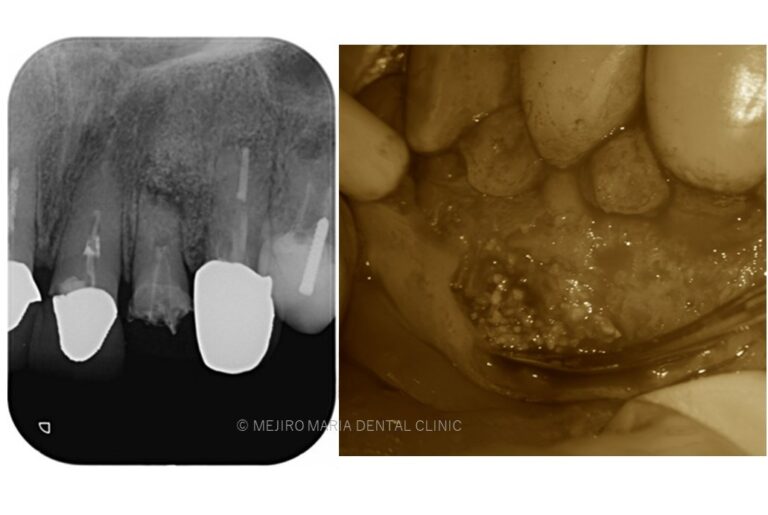

【歯根端切除術】

根管治療を行っても良くならない場合の外科的歯内療法

精密根管治療を施しても治癒に至らない場合、もしくは、被せ物を外すことが困難な場合(装着して間もない被せ物など)は歯根端切除術にて根尖性歯周炎を治癒に導くことが可能です。現代の歯根端切除術の成功率は90%以上で、破折していない歯であれば保存することが可能です。しかし、外科処置なのでリスクも当然あります。当院では精密根管治療初回カウンセリングにてご自身の歯の状態や診断から精密根管治療(歯内療法)後のリスクをお話した上で、治療介入を行うか患者様に決めていただいております。

Chapter 6

歯根端切除術(外科的歯内療法)

歯根端切除術とは口腔外科手術の一つで外科的歯内療法とも呼ばれています。細菌に感染した根管の先(根尖)を数ミリ切り取ることで感染源を取り除く治療です。もちろん麻酔をして行いますので、患者様が手術中に痛みを感じることはありません。術後の痛みは多くの場合痛み止めや消毒で対応できる程度の手術です。